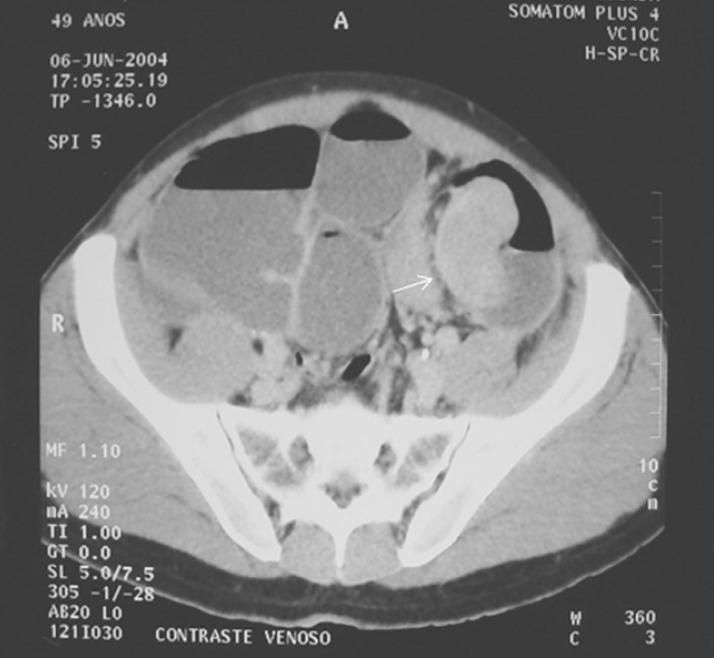

Obstrução Intestinal do Cólon

Large bowel obstruction

Obstrução Neoplásica do Cólon.